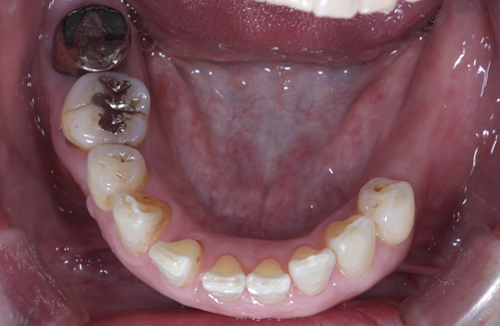

当院のインプラント治療例

― 他院で「難しい」と言われたケースにも対応 ―

※他院で骨量不足と診断された症例です。

【お悩み】

奥歯を失い、他院でインプラントの相談をしたところ「骨が足りないため難しい」と言われ、不安を感じて来院されました。

【診断】

歯科用CTにて詳しく検査を行った結果、インプラントを行うには骨量が不足している状態であることが確認されました。

【治療内容】

骨をつくる治療であるGBR(骨造成)を併用し、将来的な安定性を考慮したうえでインプラント治療を行いました。

【治療後】

現在はしっかり噛める状態となり、日常生活でも違和感なく食事を楽しんでいただいています。